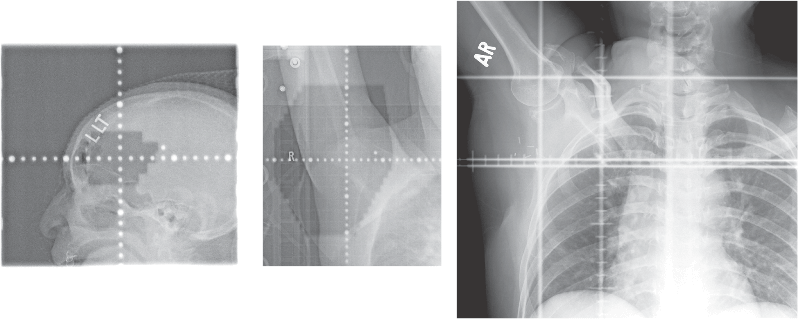

Portal radiographs are used in radiation therapy treatment to assist in simulating and visualizing the localization of radiation therapy. Fujifilm’s CR system supports Simulation and Localization (Portal Imaging). However, it is important to note that our technology does not support the third type of imaging, Verification.

(available with FCR only) for medically charged particle radiation therapy (portal localization) imaging. This exam identifies and confirms the imaging cancer treatment field and position to help identify treatment setup and adjustments. Portal images can be compared to routine radiographs to monitor irradiation field displacements. The Fujifilm PC cassette is designed to be used with FDA-cleared radiation treatment linear accelerators (LINAC) or Cobalt 60 units.